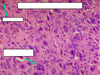

What stage of the menstrual cycle is this?